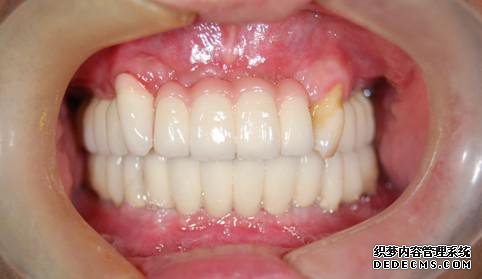

上下颌烤瓷冠修复,使患者恢复了正常的咀嚼功能,外观得到明显的改善,朱先生对修复效果十分满意。

朱先生半年后到院复查的全景片,恢复效果非常好。朱先生表示,都半年多了,没有产生任何金属过敏反应,也没有任何不适感或副作用,种植牙不仅恢复了正常的咀嚼功能,而且外观与真牙较为相似,难辨真假,甚至比真牙还要好用。